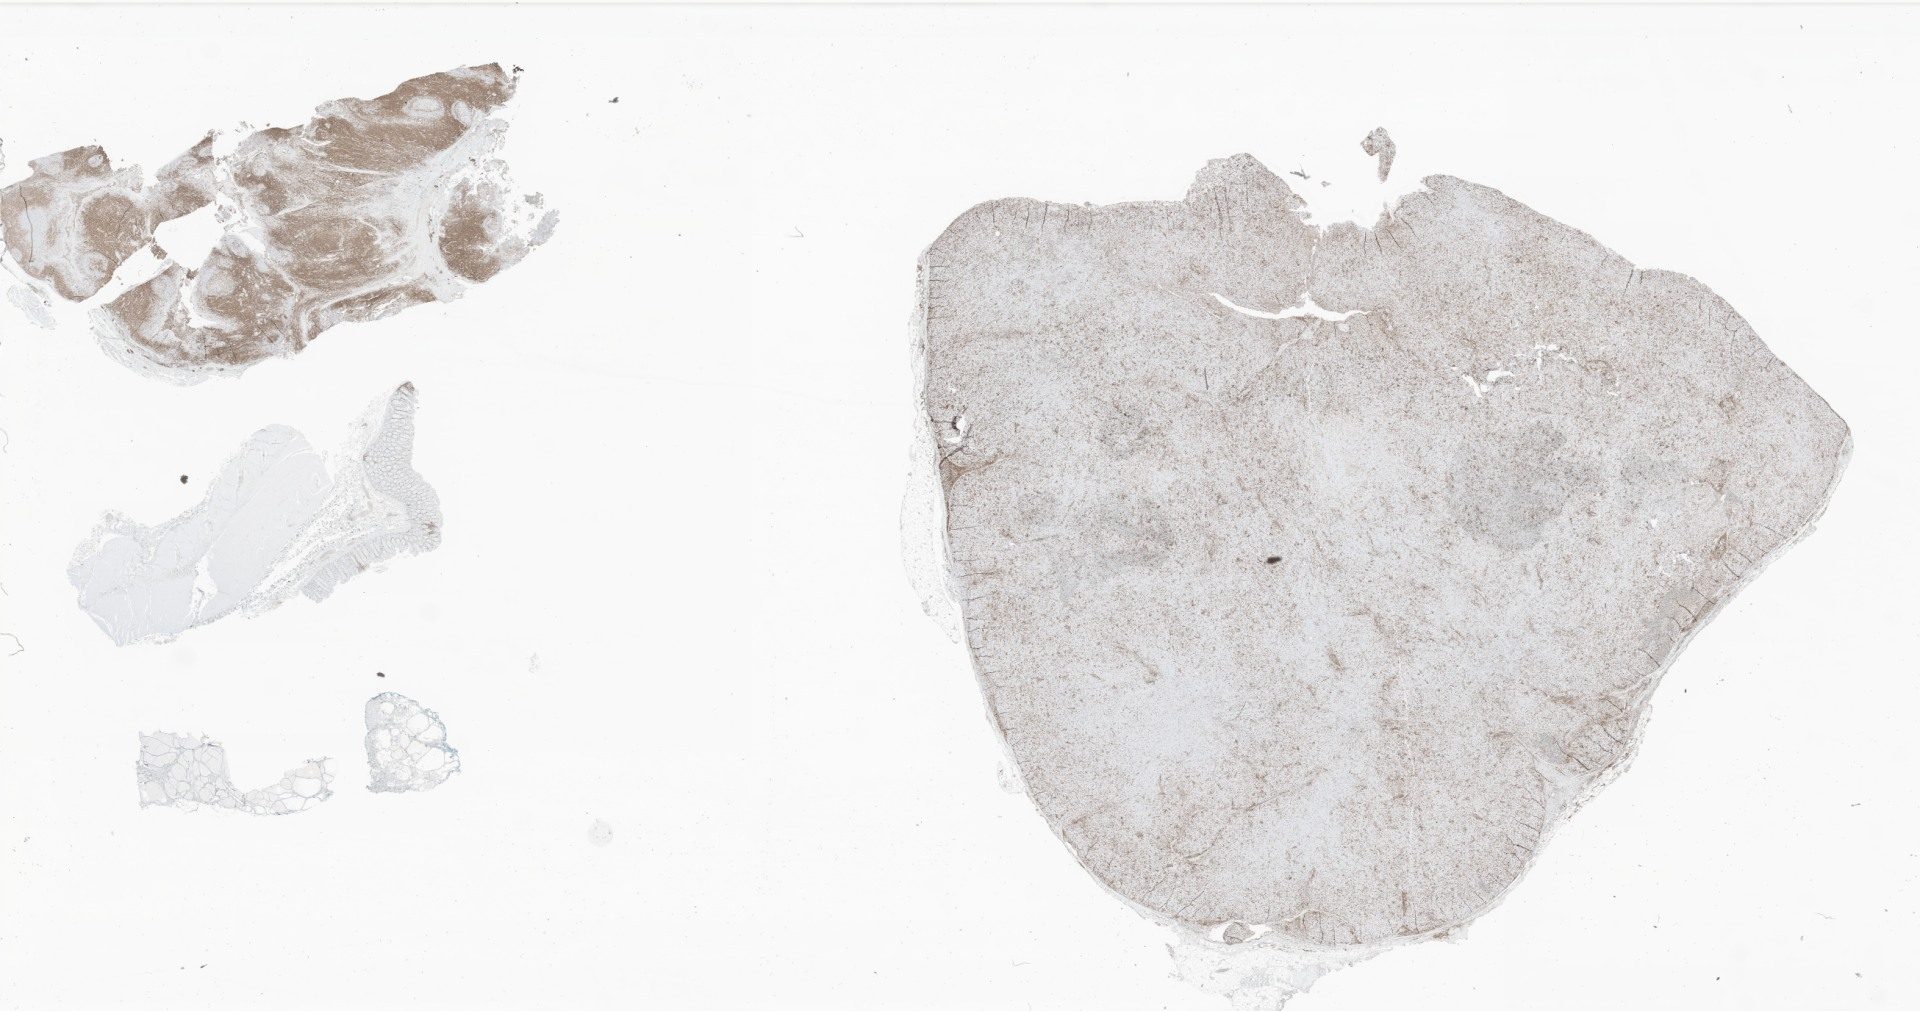

HE.svs

112002

x

88098

@

40X

LEF1.svs

118377